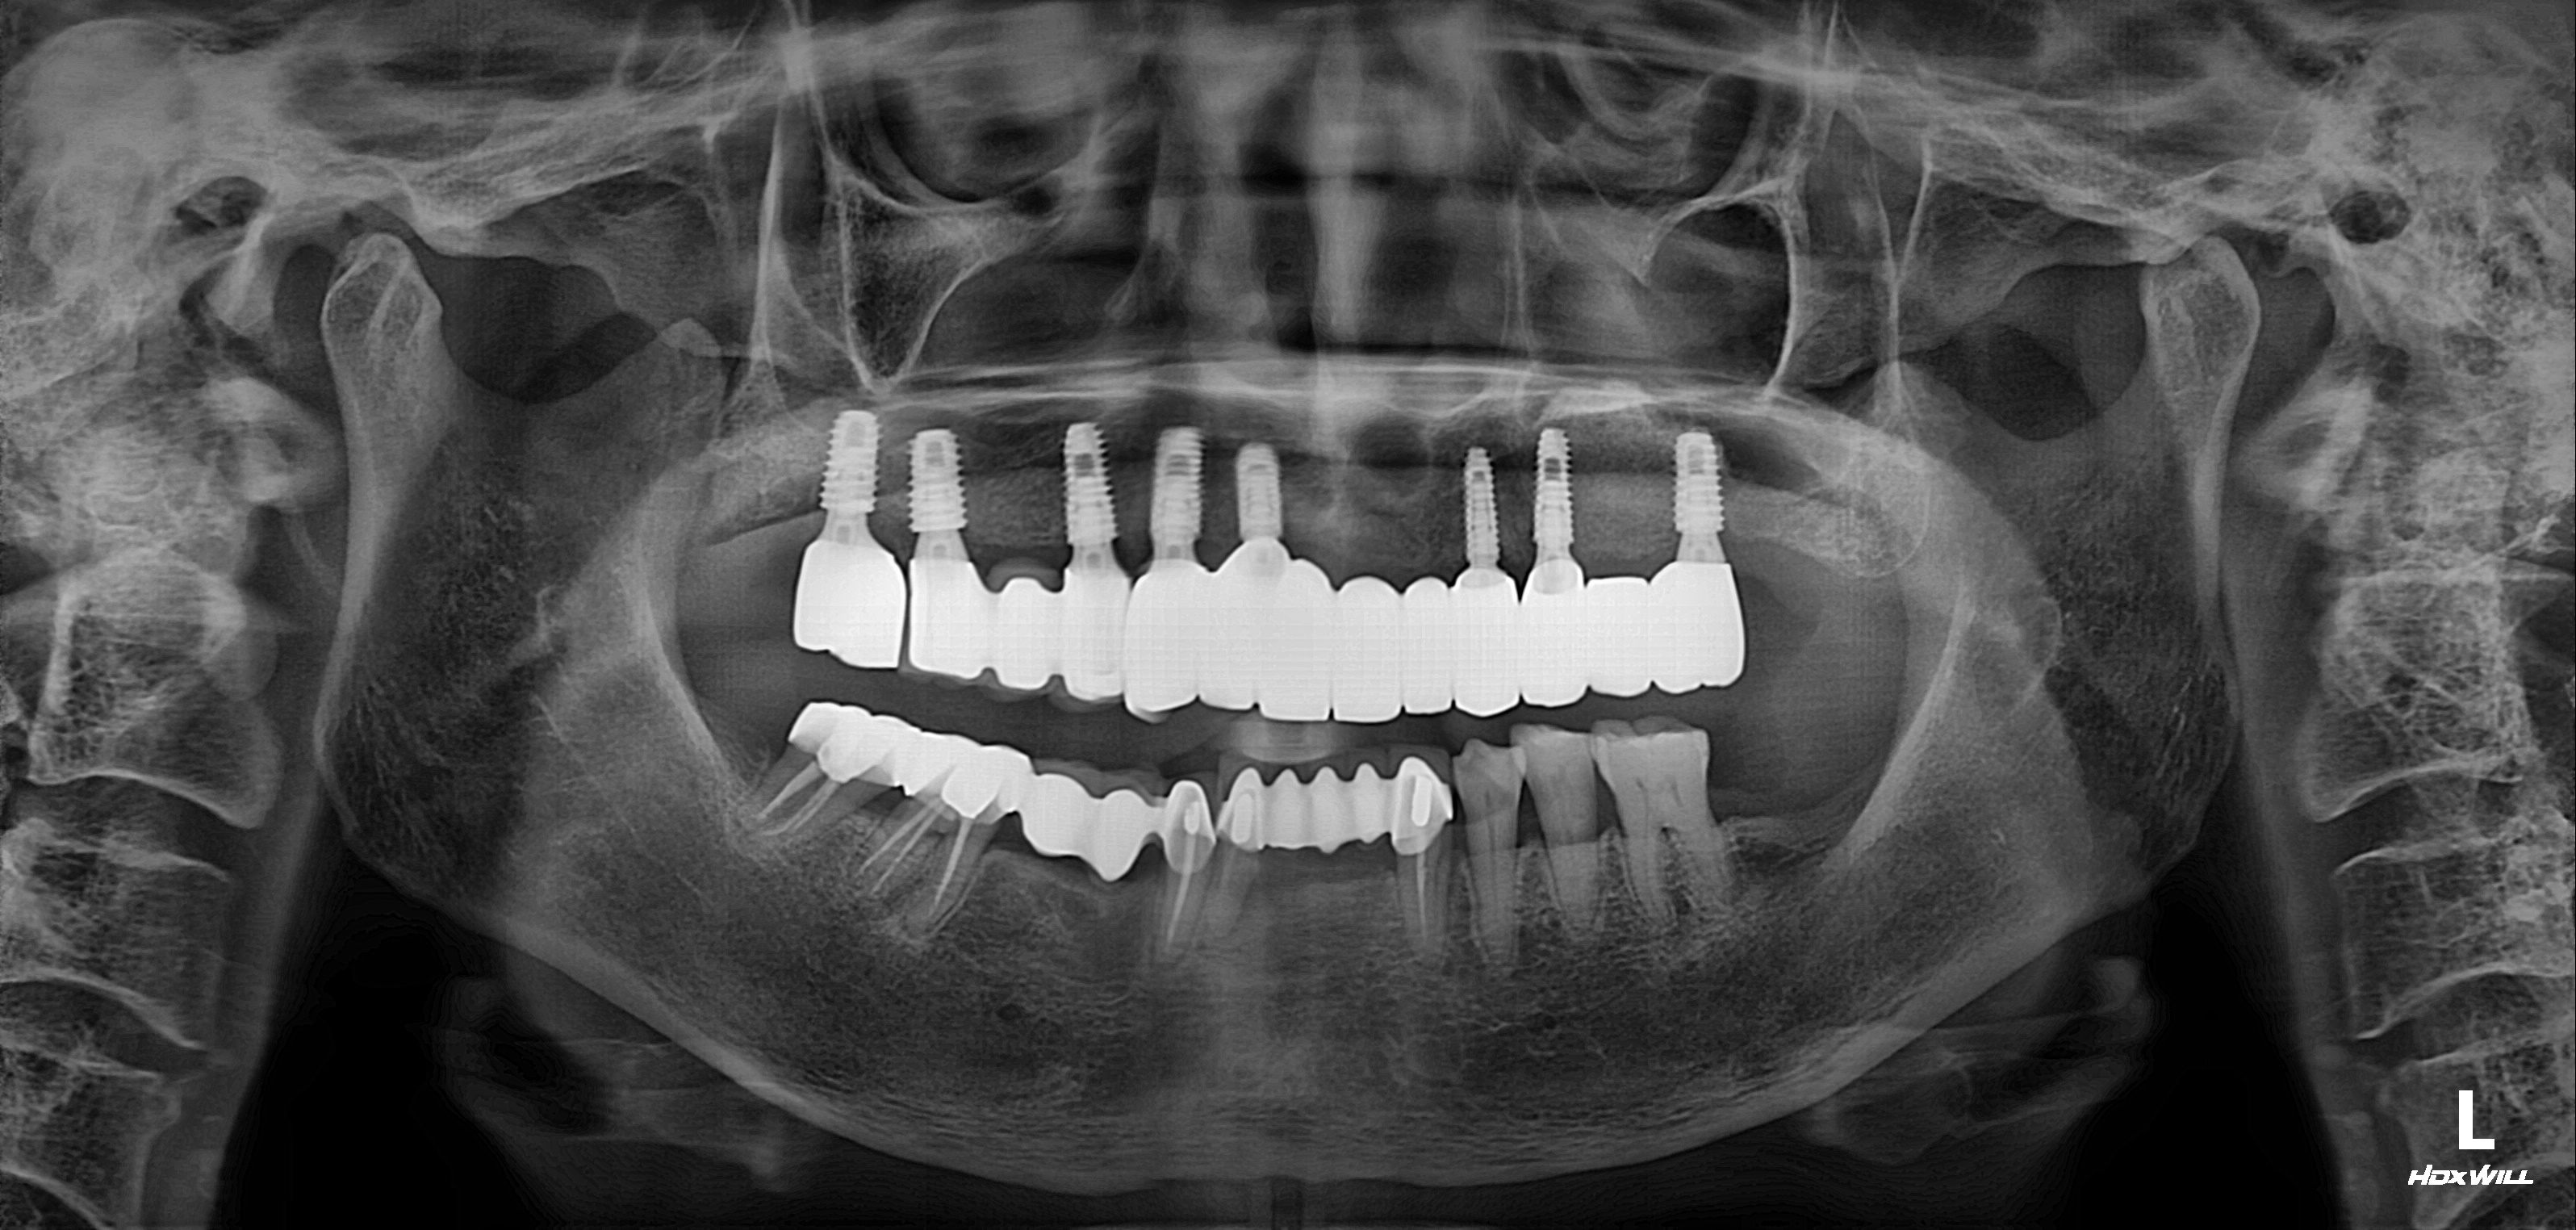

수술 전

수술 후

하악 임플란트 식립사례

전후사진

전악임플란트 식립사례